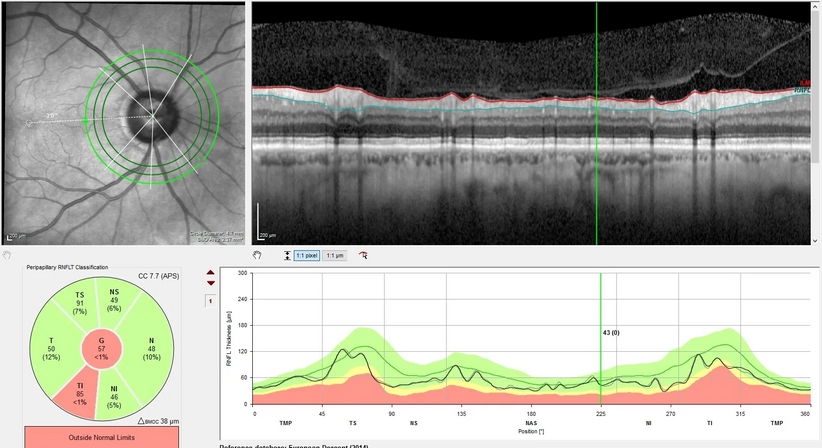

Der Begriff Grüner Star, Glaukom, umfasst Augenerkrankungen, welche – unter anderem bedingt durch einen erhöhten Augeninnendruck – den Sehnerv schädigen und bei einer unzureichenden Therapie zu einer Einengung des Blickfeldes bis hin zur Erblindung führen können. Die Verbreitung dieser Krankheit beträgt etwa 1% der Bevölkerung, wobei das Erkrankungsrisiko mit zunehmendem Alter deutlich ansteigt. Gefährlich ist vor allem der Umstand, dass sich diese Erkrankung sehr langsam und unbemerkt entwickelt und sich ein einmal eingetretener Sehschaden nicht wieder umkehren lässt. Schon ab dem 40. Lebensjahr wird deshalb eine regelmäßige Vorsorgeuntersuchung zum Zweck einer rechtzeitigen Diagnosestellung und gegebenenfalls Behandlung empfohlen. Im Falle von betroffenen Patienten in der engeren Familie wird eine Vorsorgeuntersuchung bereits früher empfohlen. Zur umfassenden Abklärung eines Glaukoms werden in unserer Ordination eine Augendruckmessung (Tonometrie), eine klinische Untersuchung des Sehnervens mittels Mikroskop, eine hochauflösenden Laser-Schichtbildaufnahme (sog. OCT, optische Kohärenz Tomographie) des Sehnervens und der Nervenfaserschicht sowie eine Gesichtsfelduntersuchung (Perimetrie) standardmäßig durchgeführt.